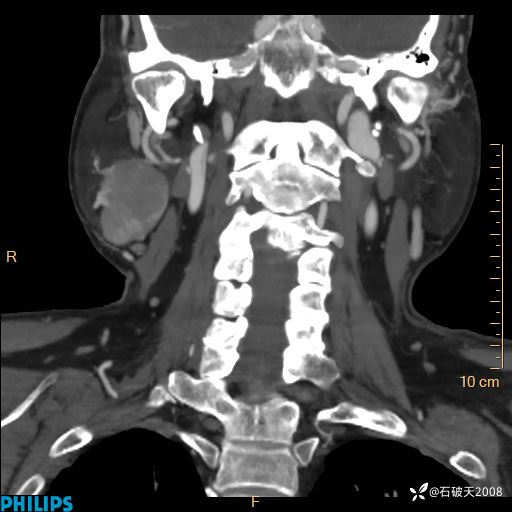

动脉期